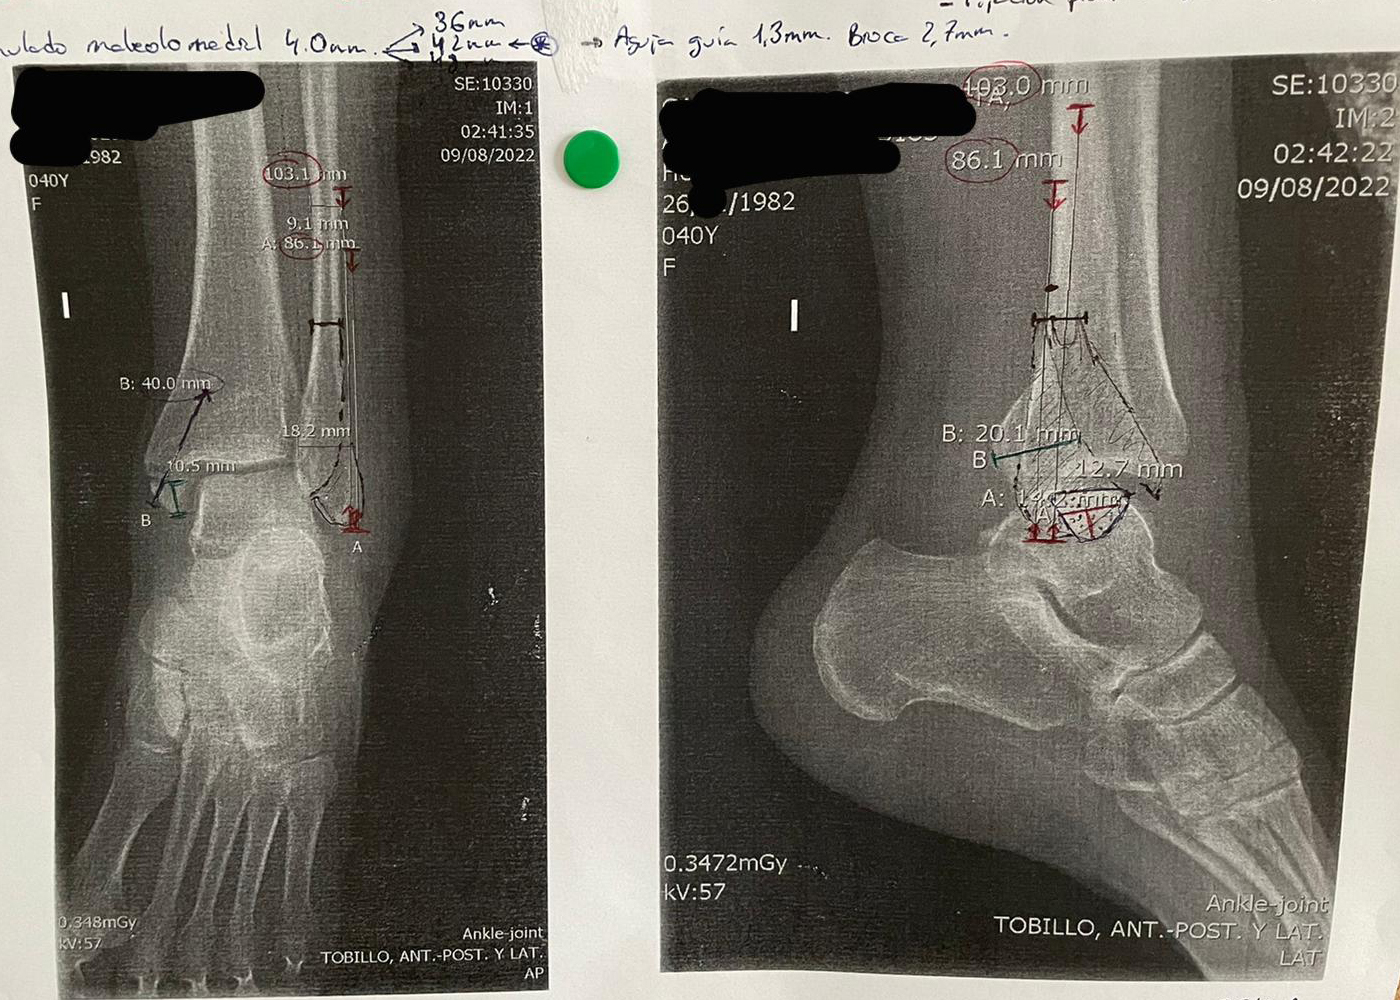

Fractura compleja de tibia y peroné, multifragmentaria, con afectación articular (Pilón) Fractura de tobillo

Fractura transindesmal de maleolo externo: se colocó un tornillo interfragmentario y una placa de 1/3 de tubo